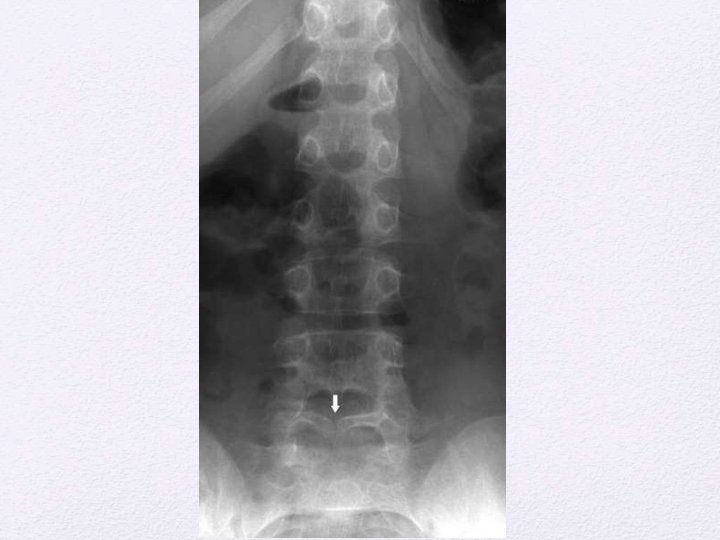

Plain radiological findings Structure Findings Lamina Fusion defects, midline defects, abnormal spinous processes Vertebral bodies Hemivertebrae, Butterfly vertebrae, Block vertebrae, Midline cleft defects, canal stenosis Disk space Congenital narrowing Pedicles Flattening, thinning Widening of spinal canal Interpedicular widening, scalloping of posterior border, Midline bony spur. Failure of development Reduced number of vertebral bodies, Absence of parts of vertebrae, sacral dysjunction Spinal curvature Scoliosis, kyphosis, lordosis.